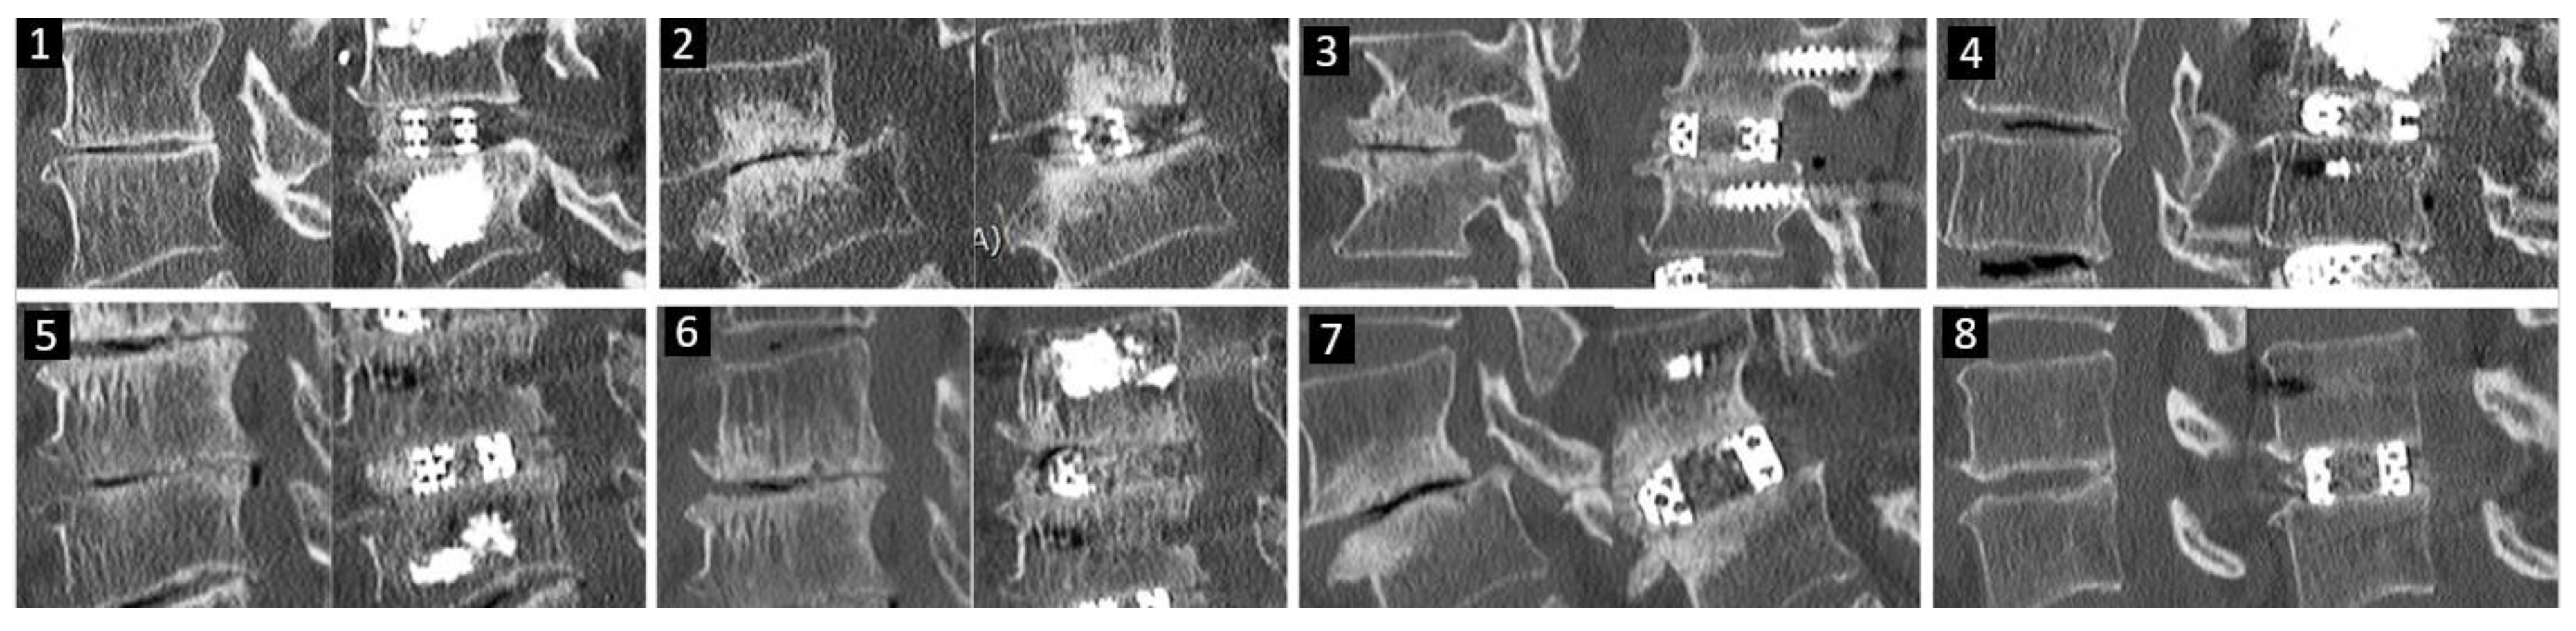

Figure 10 shows the mid sagittal CT cuts of eight different patients’ pre- and post-operative CT scans.

Figure 10. Eight different patients’ pre and post-operative mid sagittal cut CT scan showing the increase in the intervertebral disc height.